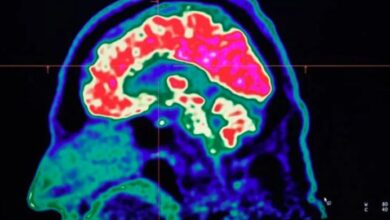

human mind

دماغ کو سمارٹ بنانے کیلئے کونسی عادات اپنانی چاہیے؟

انسانی دماغ کی خیالات کا تجزیہ کرنے کی رفتار کی حد کا تعین کا معاملہ، سائنسدانوں نے بڑا کارنامہ کر ڈالا

برطانیہ (مانیٹرنگ ڈیسک) انسانی دماغ کی خیالات کا تجزیہ کرنے کی رفتار کی حد کا تعین کا کرنے کے حوالے…